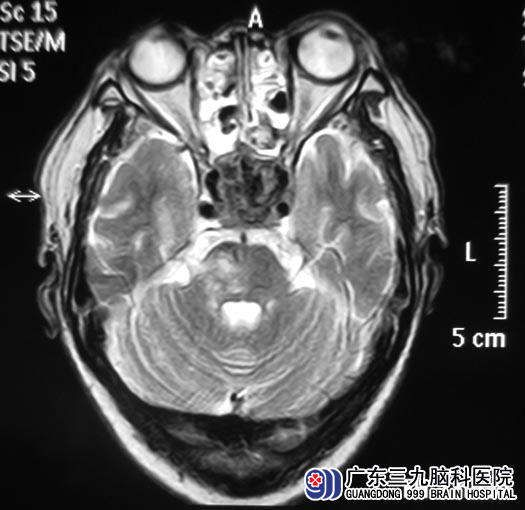

广东三九脑科医院的头颅MR检查提示:鞍区、斜坡、蝶窦部位巨大占位性病变,大小约4.61cm×2.54cm×3.63cm,内分泌检查结果提示泌乳素增高,垂体瘤诊疗中心鲁明主任考虑侵袭性垂体大腺瘤可能性大。